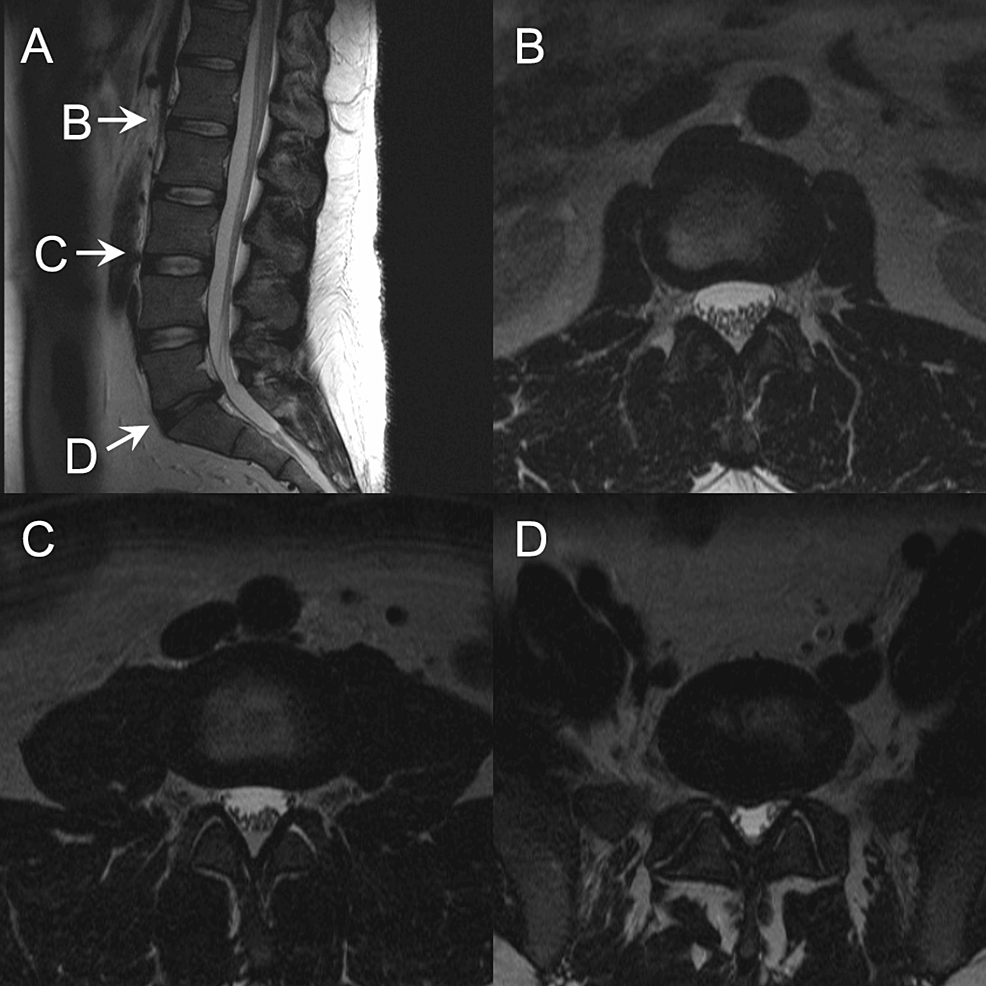

Postoperative adhesive arachnoiditis Radiology Case Adhesive Arachnoiditis Definition Arachnoiditis is a disorder caused by the inflammation of the arachnoid. Adhesive arachnoiditis is the most progressive and severe form of arachnoiditis. The arachnoid is one of the membranes that surround and. Possible causes include mechanical, chemical, inflammatory, and. Adhesive arachnoiditis is the most severe form of arachnoiditis, a neurological condition that can cause extreme pain and. Adhesive arachnoiditis is. Adhesive Arachnoiditis Definition.